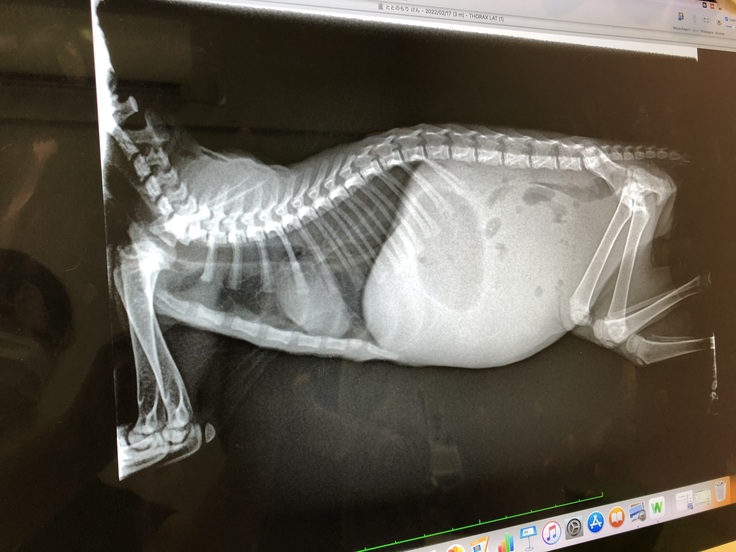

(子宮蓄膿症の雫ちゃんのお腹)